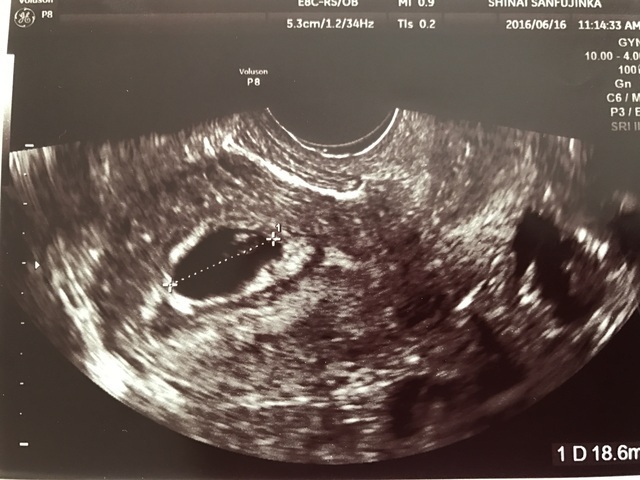

6週2日(6w2d・男の子)|じゅんぺまま さん(27歳)

エコー写真撮影時のエピソード:

2回の流産を経て、3回目の妊娠発覚後初めてのエコー写真。今まで見ることのできなかった心拍の動きにとても感動したことを覚えています。

その時すでに悪阻があり体調的には辛かったのですが、「悪阻がある=お腹の赤ちゃんが元気である」と気持ちの面では勇気付けられていました。

流産を経験しているので妊娠しても周りには伝えず、主人と喜びと不安を分け合いながら過ごしていました。